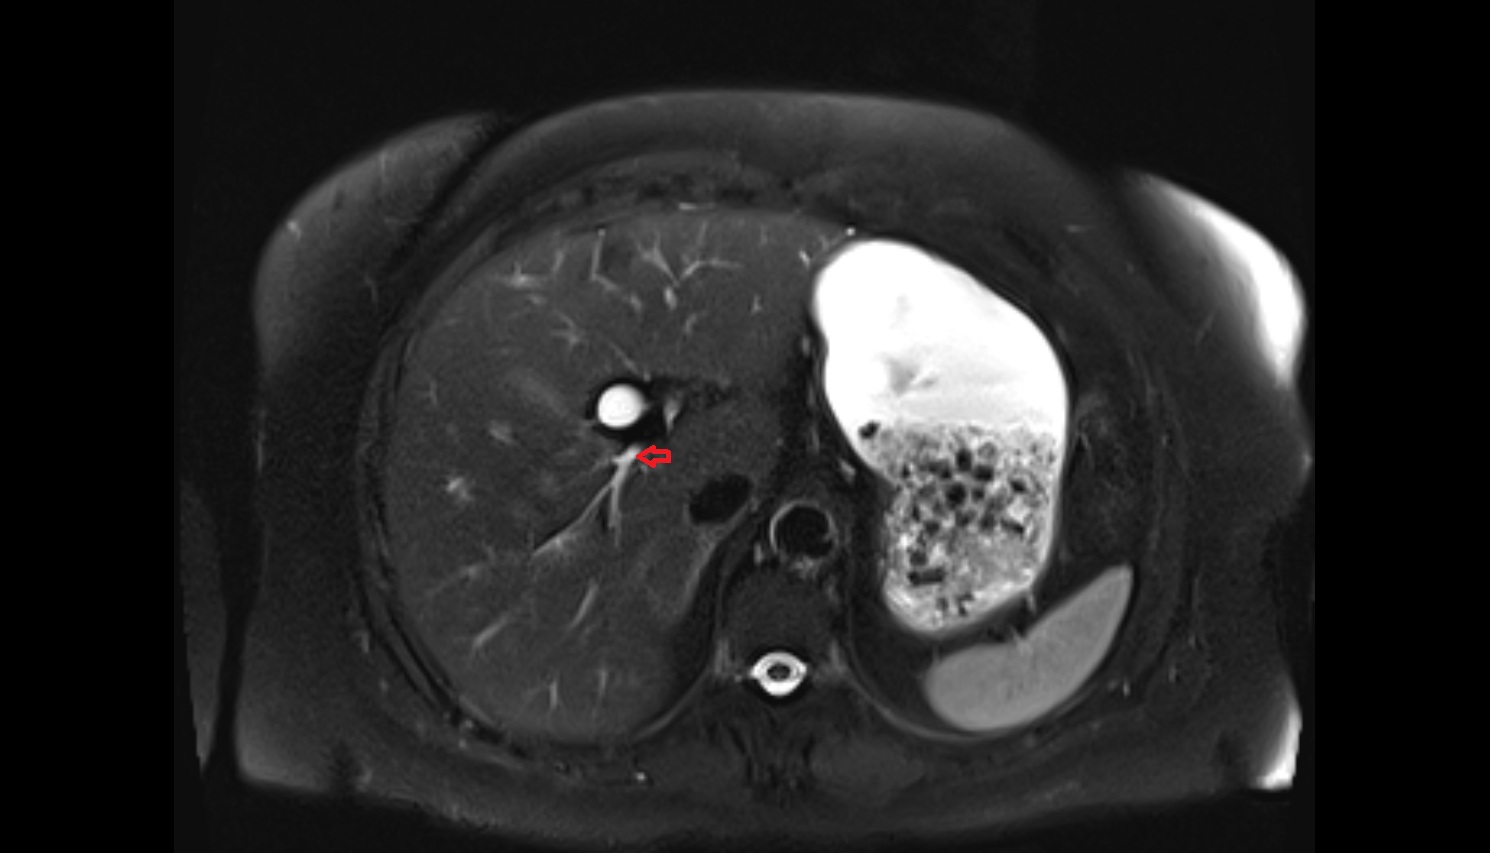

- Liver

- Spleen